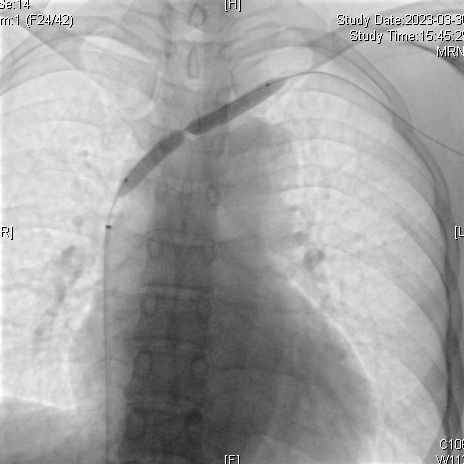

诊断:1、左头臂静脉闭塞,2、慢性肾衰竭尿毒症期,3、高血压。